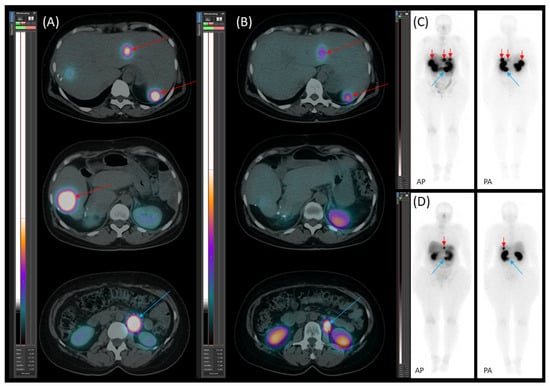

On 20 January 2022, [99mTc]Tc-EDDA/HYNIC-TOC scintigraphy with SPECT/CT identified new somatostatin receptor-expressing lesions in the liver, as well as a positive lymph node along the abdominal aorta (Figure 7). These findings represented new disease progression compared to the previous scintigraphy on 19 April 2021. Due to recurrent disease, the patient was started on somatostatin analogue (SSA) therapy with lanreotide (120 mg, once a month). The patient tolerated SSA therapy well, without experiencing any significant side effects.

Figure 7. [99mTc]Tc-EDDA/HYNIC-TOC scintigraphy with SPECT/CT. (A) Transaxial SPECT/CT, (B) transaxial CT, and (C) planar images (AP—anteroposterior; PA—posteroanterior) reveal new somatostatin receptor (SSTR)-positive lesions in the residual liver (red arrows) and para-aortic lymph node metastasis (blue arrow).